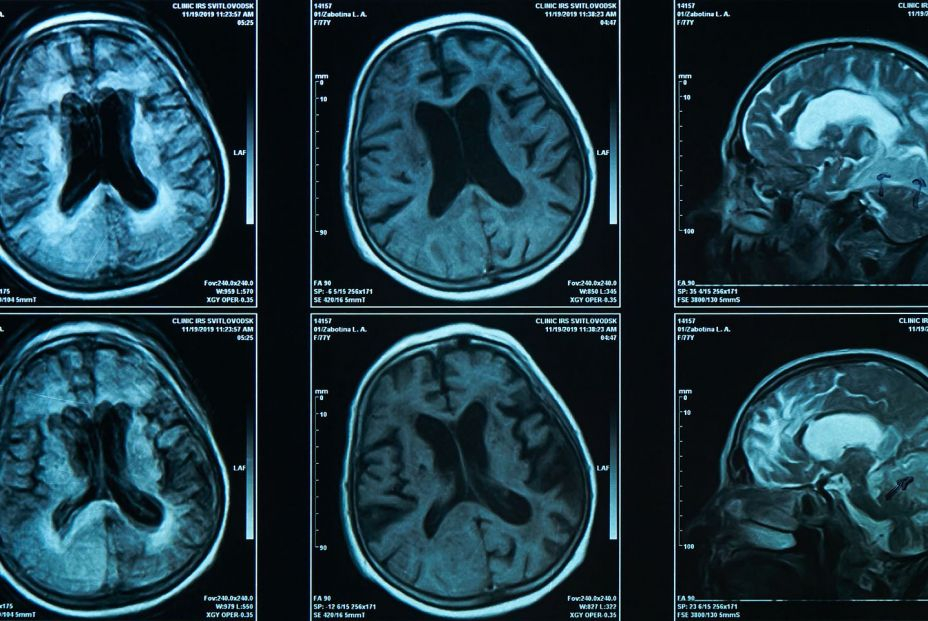

La memoria es una parte muy importante del envejecimiento, pues atesora todas las vivencias y la experiencia obtenida a lo largo de los años. Sin embargo, puede verse afectada por el envejecimiento, lo que suele conllevar también un gran golpe para la autoestima de los mayores. Por eso, los expertos inciden en la importancia de cuidarla y ejercitarla de la misma forma que se hace con el cuerpo.

Entre los profesionales que ponen en valor los ejercicios para conservar la memoria y cerebro sanos está el neurocirujano Richard Restak. En un artículo para la cadena CNBC ha incidido en la necesidad de ejercitar diariamente el cerebro para que se mantenga en buenas condiciones y favorezca la calidad de vida de los mayores.

El mensaje que difunde es claro y contundente: descuidar la salud cerebral puede aumentar el riesgo de sufrir enfermedades degenerativas, como la demencia o el alzhéimer. Para evitarlo, ha señalado siete claves que, de añadirse a la rutina diaria, serán como una sesión de gimnasia cerebral. Él, a sus 81 años, asegura que las sigue.